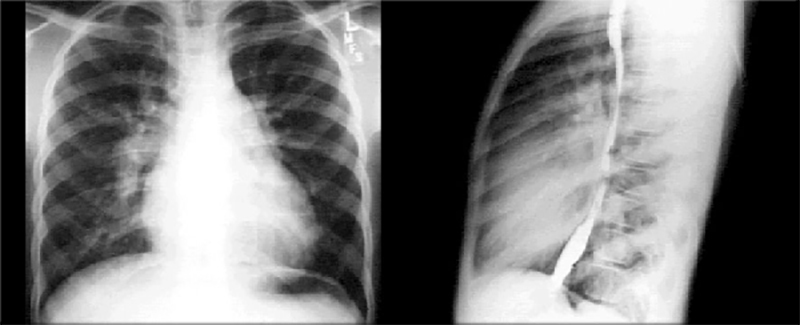

These chest X rays show right ventricular enlargement, a dilated pulmonary trunk and increased pulmonary arterial vascularity.

Right ventricular enlargement is suggested in the PA view by the

upturned apex and the minimally increased

cardiothoracic ratio.

It is suggested in the lateral view by obliteration of the

retrosternal air space.

The PA view shows dilation of the

pulmonary trunk, manifested by the convex density below the aortic knob.

Both views show prominence of the pulmonary artery, particularly well seen in the PA view as dilation of the

right pulmonary artery.

Increased pulmonary arterial vascularity is reflected further by prominent distal arterial markings. These chest X rays are consistent with a large atrial level left-to-right shunt, as in an atrial septal defect.